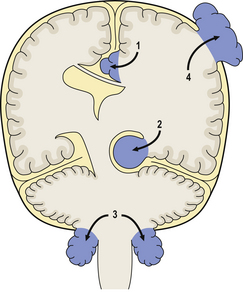

Acquired hydrocephalus can result from any lesion that obstructs the CSF pathway (Fig. 26.8). Expanding lesions in the posterior fossa are particularly prone to cause hydrocephalus, as the fourth ventricle and aqueduct are easily obstructed. Some lesions may cause intermittent obstruction, particularly colloid cysts of the third ventricle which may block the foramen of Monro. Obstructive hydrocephalus commonly results from the organisation of blood clot or inflammatory exudate in the CSF pathway following an episode of haemorrhage or meningitis (Fig. 26.9). Intermittent pressure hydrocephalus is thought to result from defective CSF absorption at the arachnoid villi.

image

Fig. 26.9 Longstanding hydrocephalus. image The lateral ventricles are very dilated and contain a prominent choroid plexus (arrow). The overlying white and grey matter are atrophic. Fibrous adhesions are present in the ventricles posteriorly, suggestive of previous infection. image In the same case, the cerebral aqueduct in the midbrain is completely obliterated by glial tissue as a consequence of a previous viral infection (arrow). This has resulted in obstructive hydrocephalus.

The complications of hydrocephalus can be averted or relieved by the insertion of a ventricular shunt with a one-way valve system to drain CSF into the peritoneum. Untreated patients may suffer irreversible brain damage (Fig. 26.9). Ventricular shunts often need to be replaced in growing children and are prone to become infected with low-virulence bacteria, for example Staphylococcus epidermidis. Infection may result in shunt blockage and exacerbation of symptoms attributable to raised intracranial pressure.